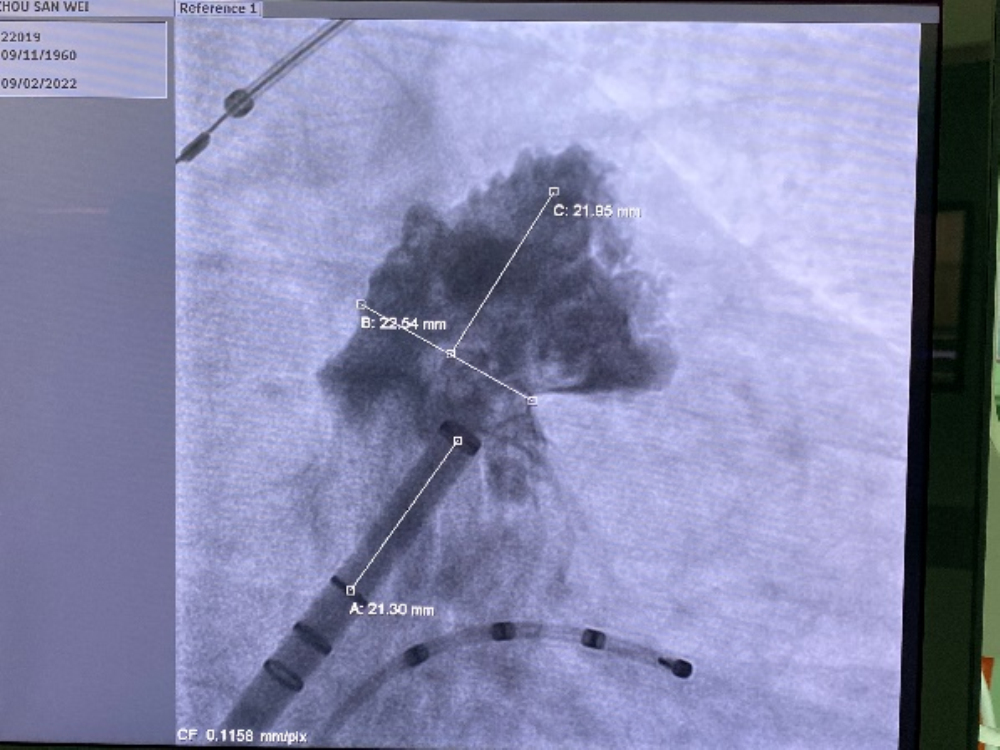

术中DSA造影测量图

术中DSA影像图